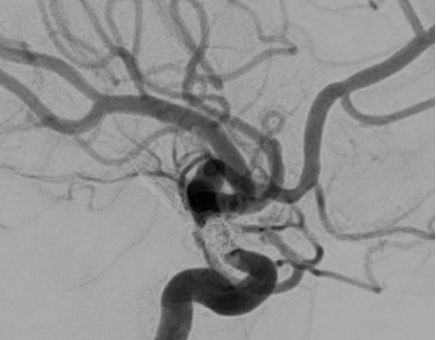

Flow Diversion

The FDA approval of flow diversion technology in 2011 revolutionized the treatment of intracranial aneurysms. The use of this technology has rapidly evolved, extending beyond paraclinoid aneurysms to include the treatment of distal and complex aneurysms, even those located in the posterior circulation. Our research focuses on establishing the safety and efficacy of flow diversion for both FDA-approved and off-label use, factors determining treatment failure, complications, adjustments to dual antiplatelet therapies, and ideal imaging follow-up intervals. We have also explored biological mechanisms predicting response after treatment and collaborated with multiple institutions nationwide in various registries and clinical protocols.